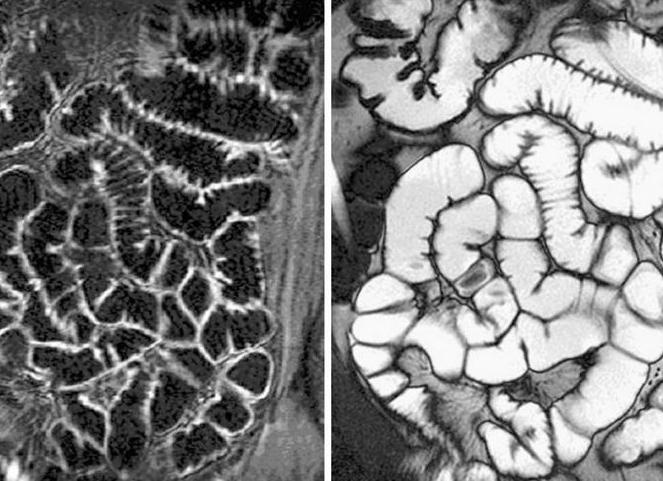

Сравнительная оценка КТ-энтерографии (Рис. 8, 9) с рентгенологическим методом исследования проведена на 65 пациентах. Из них у 16 (24,6%) человек болезнь Крона не подтверждена ни одним из указанных методов. У 4 (75,4%) больных выявлена болезнь Крона, из них у 35 (71,4%) пациентов выполнено хирургическое вмешательство с верификацией заболевания. 14 (28,6%) больных с установленным диагнозом не оперированы.

Рисунок 8,9. Исследование тонкой кишки методом пассажа бария, КТ-энтерография, аксиальный срез. Картина болезни Крона, осложнённой воспалительным инфильтратом, неполным внутренним свищом с полостью

Анализ сравнения результатов рентгеновского и КТ исследований был сопоставим. При рентгеновском исследовании так же выявлялись свищи и инфильтраты, отчётливо прослеживалась локализация изменений и их протяжённость. В 4-х недостоверных случаях КТ диагностики болезни Крона, рентгенологически так же выявлялись нетипичные признаки, в виде дистонии терминального отдела, а заключения были не конкретные.